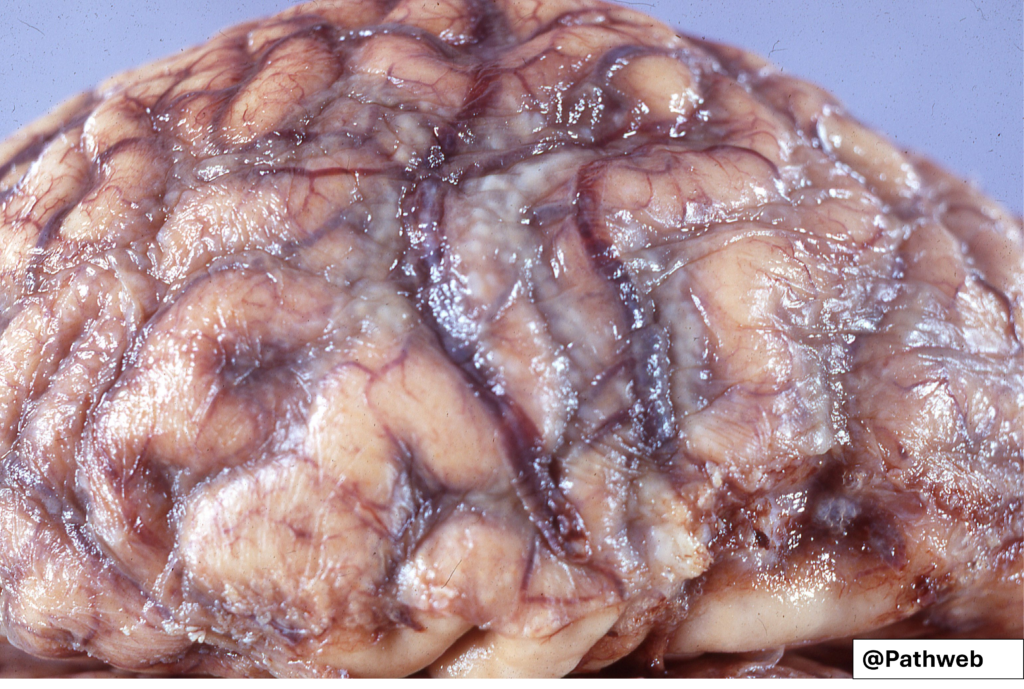

45 year old man with pulmonary tuberculosis was admitted for headache, malaise, fever, mental confusion and vomiting. He had progressive neurologic deficits over some time.

CSF analysis showed mononuclear cells, some neutrophils, elevated protein concentration and moderately reduced glucose

There is a pale tan fibrino-inflammatory exudate over the base of the brain within the subarachnoid space. The exudate effaces the cisterns and encases the cranial nerves. Arachnoid fibrosis has set in, resulting in internal hydrocephalus.

Microscopy would show mostly chronic inflammatory cells, granulomatous inflammation and necrotic cellular debris.

Brain: TB meningitis and infection

Brain: Tuberculous meningitis (Gross pathology)